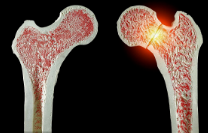

髋部骨折是老年人最严重的骨质疏松性骨折,具有高致残率和致死率。手术技术的提高和多学科协作管理模式对改善患者预后具有重要作用,也对围术期护理提出了更高要求。患者整体功能衰退、器官合并症增多、麻醉及手术对机体储备的二次打击使护理难度增加,且我国尚缺乏对于老年髋部骨折患者围术期护理的规范来指导临床实践。因此,中华护理学会骨科护理专业委员会组织相关专家,基于循证医学方法,制订《老年髋部骨折围术期护理临床实践专家共识(2023版)》,围绕老年髋部骨折围术期健康教育、病情监测与观察、并发症风险评估与预防、康复训练等方面提出11条推荐意见,以指导临床实践,提升围术期护理质量,改善老年髋部骨折患者预后。